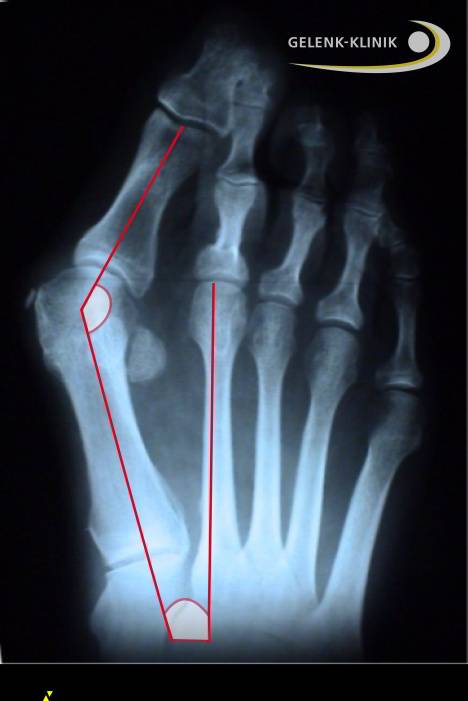

Röntgen zeigt das Ausmaß des Hallux valgus

Zusätzliche Informationen über das Stadium des Hallux valgus gibt ein Röntgenbild des Fußes. Dabei misst der Arzt im Stehen – also unter Belastung – die exakte geometrische Abweichung der Fehlstellung von der Normalstellung. Diese Abweichung bezeichnet der Mediziner als Hallux valgus-Winkel. Die Kernspintomographie (MRT) kann Knorpelschäden, Weichteileinklemmungen und Knochenschäden feststellen.

Stadien des Hallux valgus

- Eine Großzehenstellung mit einem Winkel von bis zu 10° gilt als normal.

- Eine milde Hallux valgus-Fehlstellung liegt zwischen 16° und 20° vor.

- Eine mittlere Hallux valgus-Fehlstellung weicht zwischen 21° und 40° ab.

- Eine schwere Hallux valgus-Fehlstellung weicht über 40° ab.